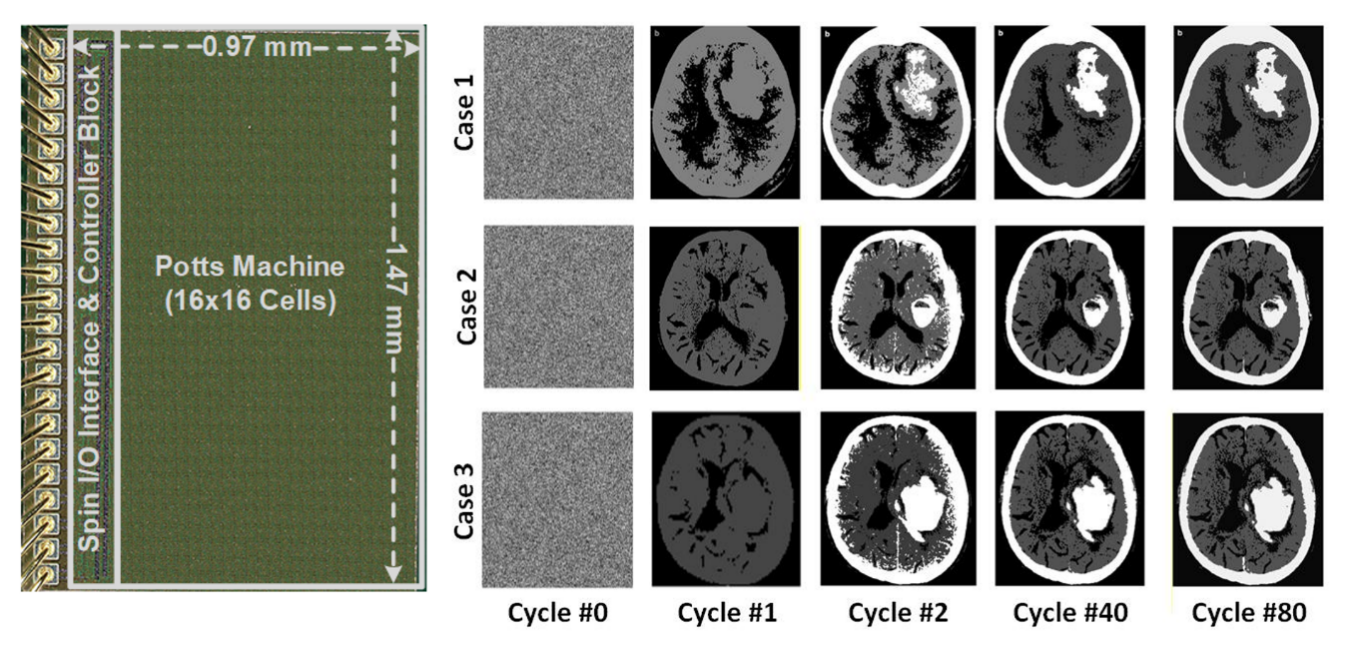

为攻克这一难题,我校半导体学院陈卓俊教授团队成功研发出面向复杂组合优化问题的全集成波茨机处理器芯片。该芯片基于65nm CMOS工艺制造,集成256个自旋单元,支持2至4比特耦合系数位宽及King’s Graph自旋网络拓扑,单个自旋面积仅为4400 μm²。芯片已在CT图像聚类、合金相变模拟等实际应用中完成验证,展现出优越的面积效率与能效表现。

研究团队在架构、电路和算法层面实现了三重创新:提出可重构波茨机架构,支持每个自旋单元表达多达四种状态;通过自旋内外系数复用策略,显著降低硬件面积成本,实现了目前所有同类工作中最小的归一化自旋面积;受晶体结晶过程启发,提出逐次边界逼近退火算法,在图像聚类等任务中求解速度达传统模拟退火方法的10倍。

波茨机芯片的架构图与波茨单元的示意图。

波茨机芯片的显微图及其在CT图像聚类中的应用。